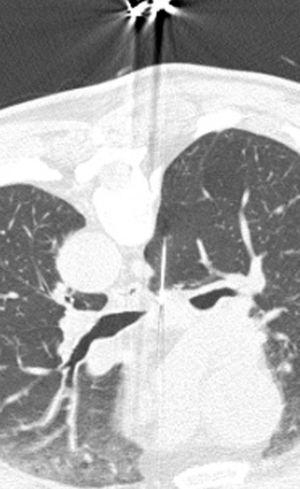

Pese a las conocidas limitaciones de la TC, ésta continúa siendo la técnica de elección en la estadificación del tumor en los pacientes con CPNM; su sensibilidad y especificidad en la determinación de la infiltración de pared oscilan entre el 38 y el 87% y del 40 al 90%, respectivamente, según las series. El desarrollo de nuevos equipos de TC helicoidal y principalmente las TC multidetectoras (TCMD) proporcionan unas imágenes 2D de mayor resolución con la posibilidad de hacer reconstrucciones multiplanares (MPR) en distintos planos del espacio e incluso 3D con la consiguiente mejora de la valoración del tumor, su extensión e infiltración de estructuras vecinas5 (fig. 4). Así, con la TCMD se puede poner de manifiesto con mayor fiabilidad la invasión de la cisura, la pared torácica o el mediastino, y además es capaz de determinar, gracias a las reconstrucciones de volumen, la relación exacta del tumor con la vía aérea (fig. 5). El progreso en la capacidad diagnóstica deriva del incremento en la resolución de las imágenes obtenidas y de la posibilidad de emplear nuevas aplicaciones como la broncoscopia virtual y la visualización en tiempo real. La broncoscopia virtual es útil para valorar la invasión del árbol traqueobronquial con la finalidad de planificar la cirugía, también como guía para el fibrobroncoscopista y, por último, porque permite ver el árbol bronquial distal a la estenosis (fig. 6)6. La capacidad de ver la imagen en tiempo real es especialmente útil cuando se emplea como guía en maniobras intervencionistas como biopsias percutáneas, ya sea con finalidad diagnóstica o como parte de la estadificación (fig. 7). Esta técnica de guía de biopsia denominada TC fluoroscopia reduce el número de pases y el tiempo global de la exploración, implica un menor riesgo de lesión de estructuras y permite la visualización inmediata de las posibles complicaciones7.

También el empleo de la TC como guía para la obtención de muestras que ayuden en la estadificación mediante PAAF o biopsia es de gran utilidad en aquellos territorios ganglionares no accesibles a la mediastinoscopia, como el espacio subcarinal (fig. 7), pudiendo en otras ocasiones sustituirla como técnica menos cruenta.